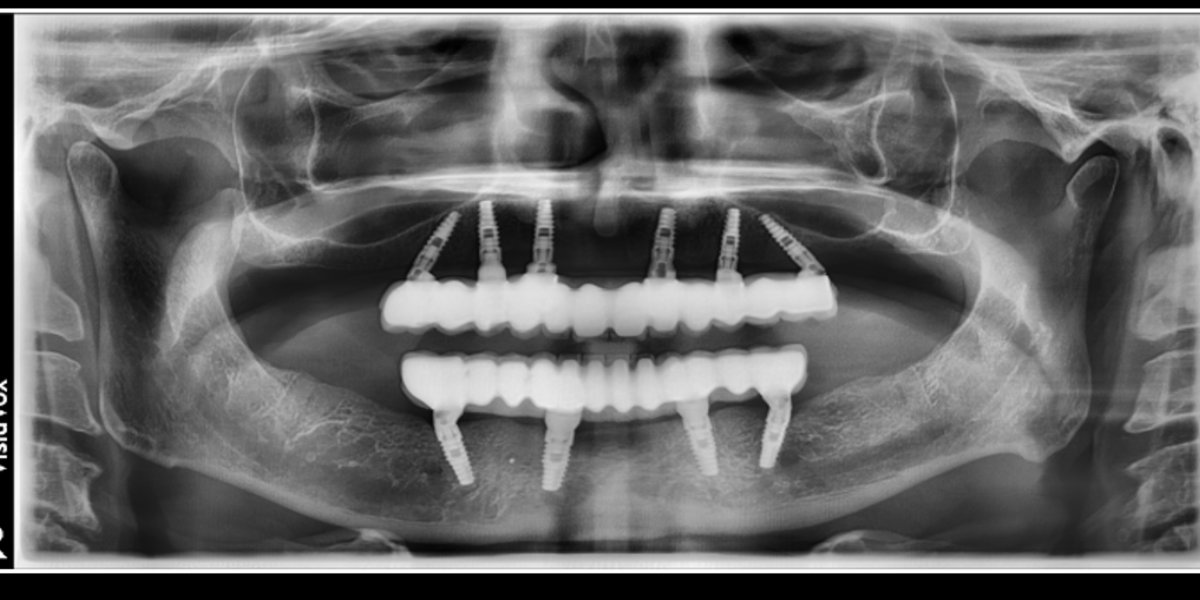

Dental Implants — OPG

Diagnostic radiograph case

OPG views showing precise implant placement and integration. Imaging-guided planning is at the core of every implant case here.